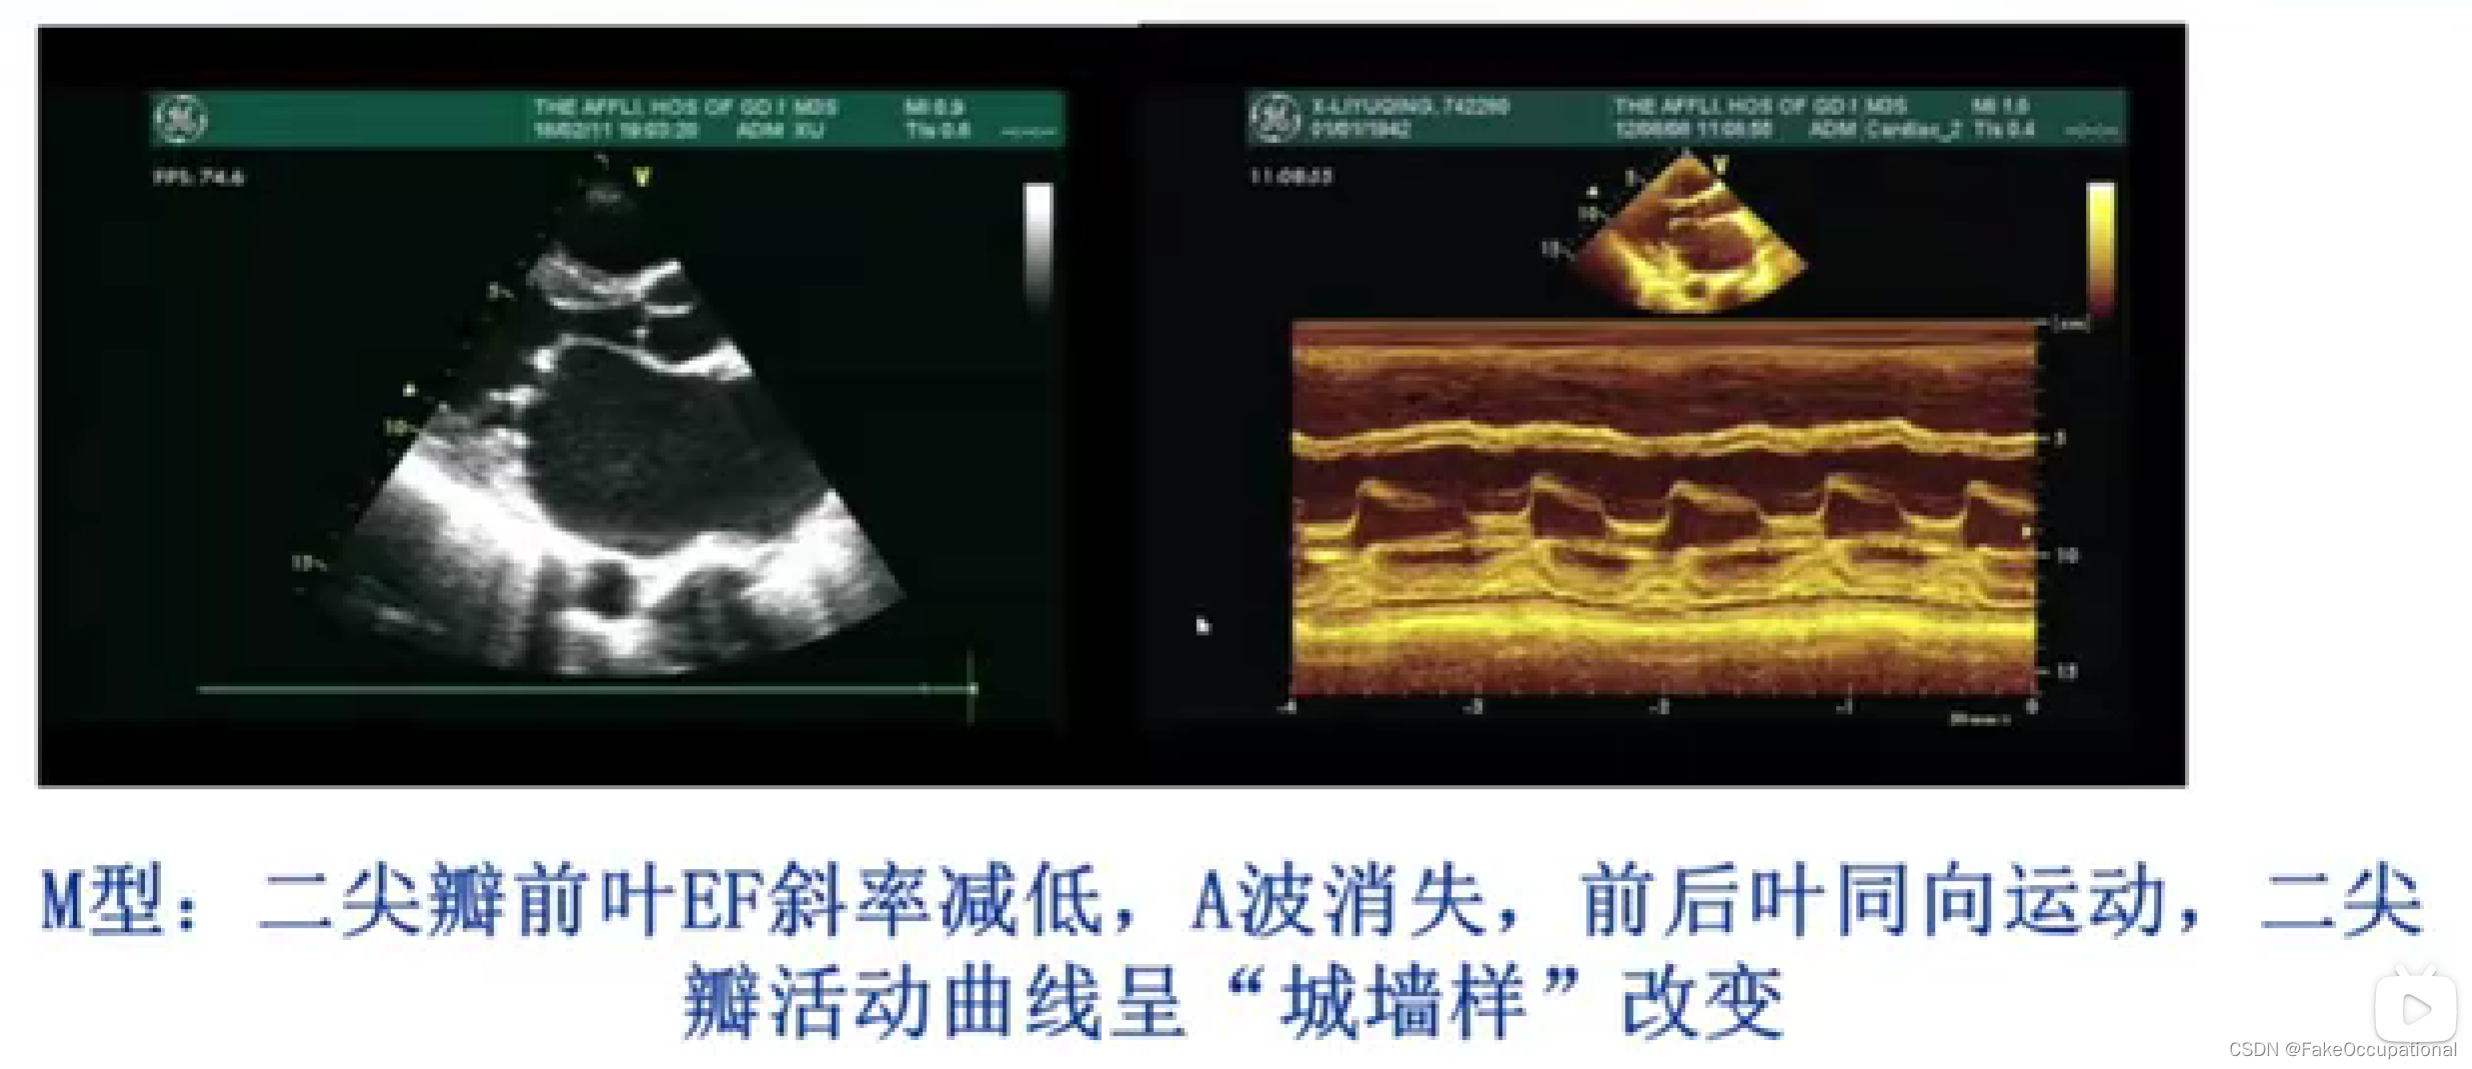

冠心病超声诊断

室壁运动超声评分标准:

运动正常- 1分

运动减弱- 2分

运动消失 - 3分

矛盾运动 - 4分

室壁瘤形成-5分

室壁运动指数 (WMSI) =冬节段得分之和/参与评分的节段数

左室各节段收缩功能正常者WMSI为1分WMSI越大,左室收缩功能受损程度越重